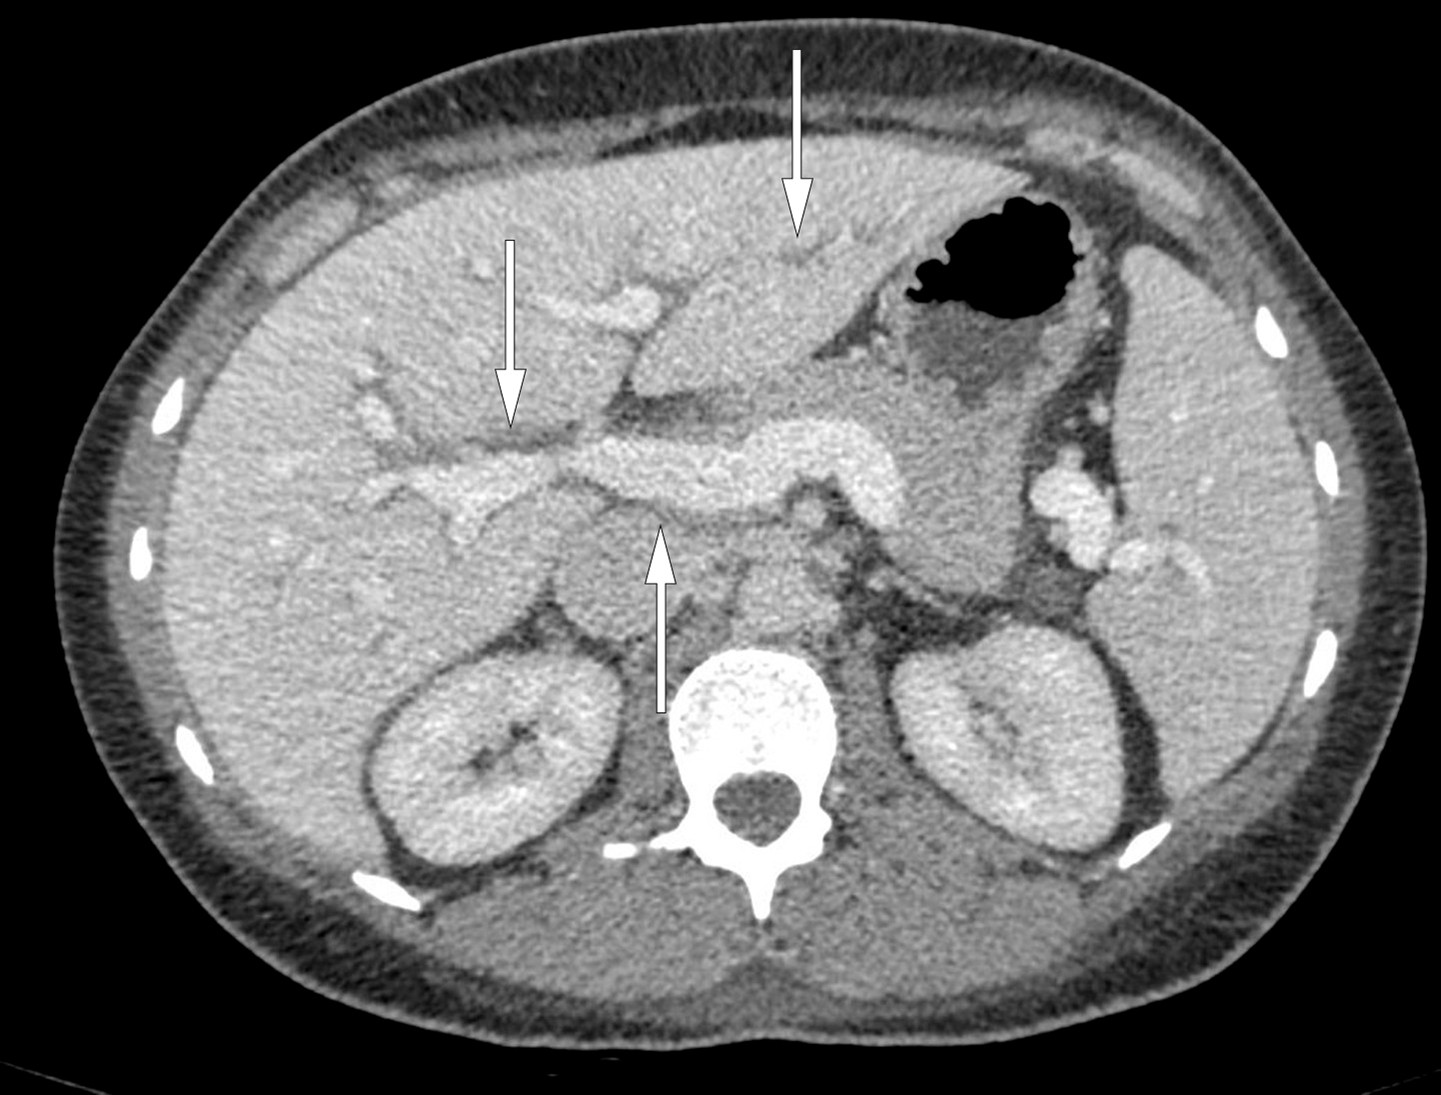

Pasienten hadde altså nyreaffeksjon presentert klinisk med hematuri, proteinuri og kreatininstigning. Ultralyd abdomen og senere CT thorax/abdomen viste flere funn: multiple forstørrede lymfeknuter i armhule, mediastinum, lysker og paraaortalt, hvor største lymfeknute i venstre lyske målte 0,5 × 2 cm. Videre viste CT ødem i mediastinalt fettvev, periportalt ødem i lever og galleblærevegg (figur 1), bilateral pleuravæske og små mengder ascitesvæske. Hun hadde anemi og trombocytopeni, men ikke mangel på jern, vitamin B12 eller folat. Det var ingen hemolyse. Hemofec var negativ. Pasienten hadde ikke hatt menstruasjon på lenge grunnet hormonspiral. Senkningsreaksjon, C-reaktivt protein, leukocytter og laktatdehydrogenase var normale. Blodprøver viste lavt nivå av C3 (komplementfaktor) på 0,57 g/l (0,90–1,8 g/l) og normal C4 forenelig med akutt, postinfeksiøs glomerulonefritt. Prøver for antinukleære antistoffer, antinøytrofile cytoplasmiske antistoffer (ANCA), antistoffer mot glomerulus basalmembran, anti-cykliske citrullinerte peptider og revmatoid faktor var negative. Følgelig var systemsykdommer som systemisk lupus erythematosus, ANCA-positiv vaskulitt og Goodpastures syndrom lite sannsynlige årsaker til dette kliniske bildet.